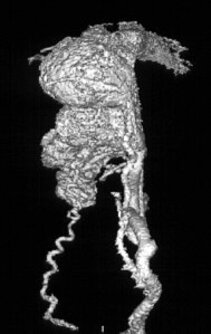

Bei einer Arteriovenösen Malformation, auch Angiom genannt, fehlt dieser Sauerstoffaustausch, das Blut fließt durch eine Kurzschlussverbindung (Nidus). Dieser stellt sich in der Bildgebung als ein Gefäßkonglomerat dar.

Angiographische Darstellung eines Angioms in 3D-Darstellung.